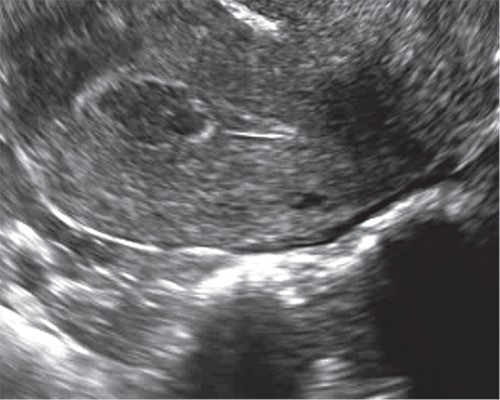

В ходе проводимой нами эхометросальпингографии с использованием в качестве контраста стерильного физиологического раствора также становится возможной визуализация мелких полипов эндометрия и внутриматочных синехий (рис. 3).

Рис. 3. Мелкий полип эндометрия на фоне эхонегативной контрастной среды (стерильный физиологический раствор) в ходе эхогистероскопии.